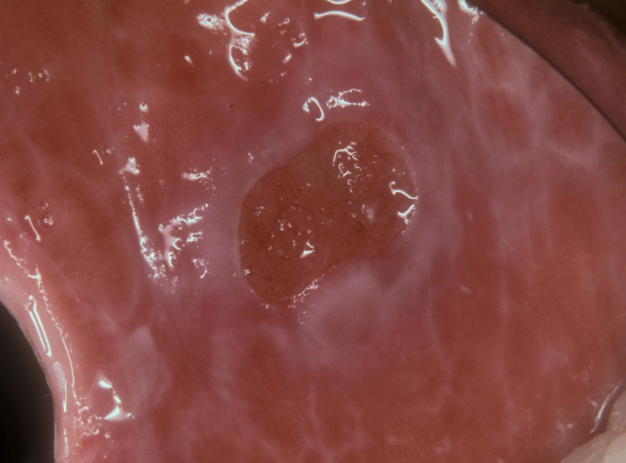

Histopathologic Features of what condition?

• Sub-epithelial separation below basal layer (SUB-basilar cleavage)

• Mimics linear IgA disease, epidermolysis bullosa acquisita, and angina bullosa hemorrhagica

Mucous Membrane Pemphigoid